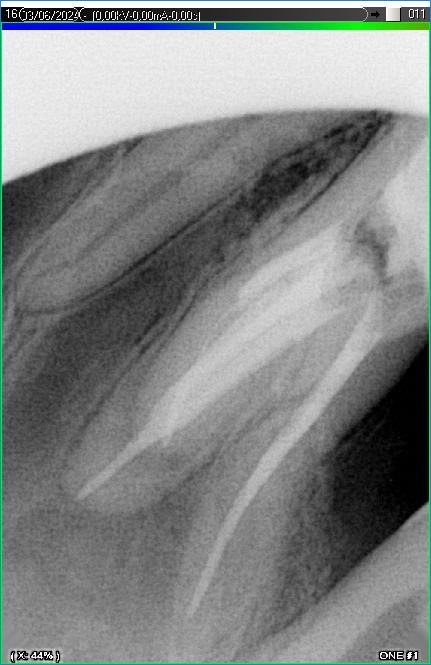

Вилучення інструменту з каналів зуба